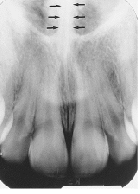

Cortical Bone

dense outer layer of bone

(radiopaque)

Cancellous Bone

soft spongy bone between cortical plates

(radiolucent)

Nasal Cavity/Fossa

large radiolucent area above the max incisors (aka nasal fossa)

Nasal Septum

vertical radiopaque divider in the nasal cavity

Floor of Nasal Cavity

dense radiopaque band of bone above the max incisors

Inferior Nasal Conchae

diffuse radiopaque projection in the nasal cavity